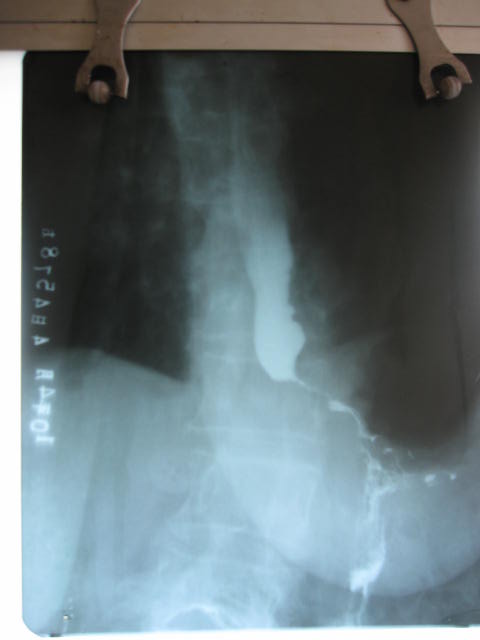

以下是引用随光逐影在2010-4-4 17:45:00的发言:[br]胃底贲门癌可能性大;建议行胃镜检查(活检)进一步明确诊断。

以下是引用zsl6918在2010-4-4 17:40:00的发言:[br]高度警惕胃底贲门癌

以下是引用沉默是金在2010-4-4 15:27:00的发言:[br]考虑贲门癌,建议胃镜活检